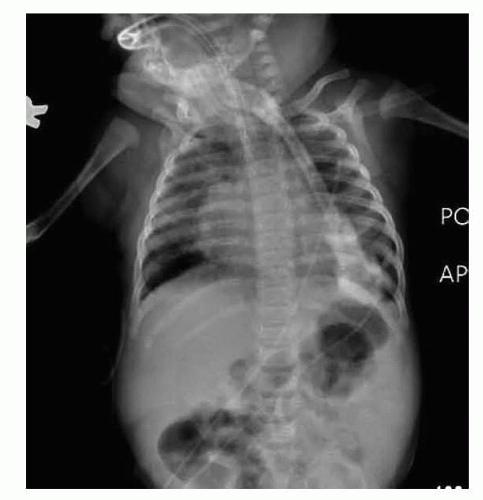

Floating ribs (11,12) do not attach to the sternum (plain film; FIG 2).